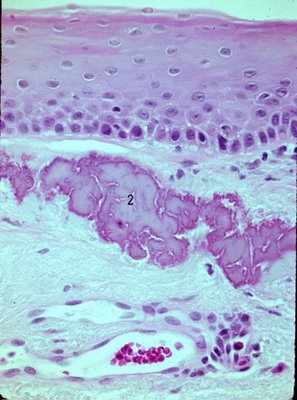

조직 병리 소견상

상피하, 보우만층, 각막기질에서 hyaline 양 물질의 침착이 보이며,

진행되는 경우, 상피도 침범하게됩니다.